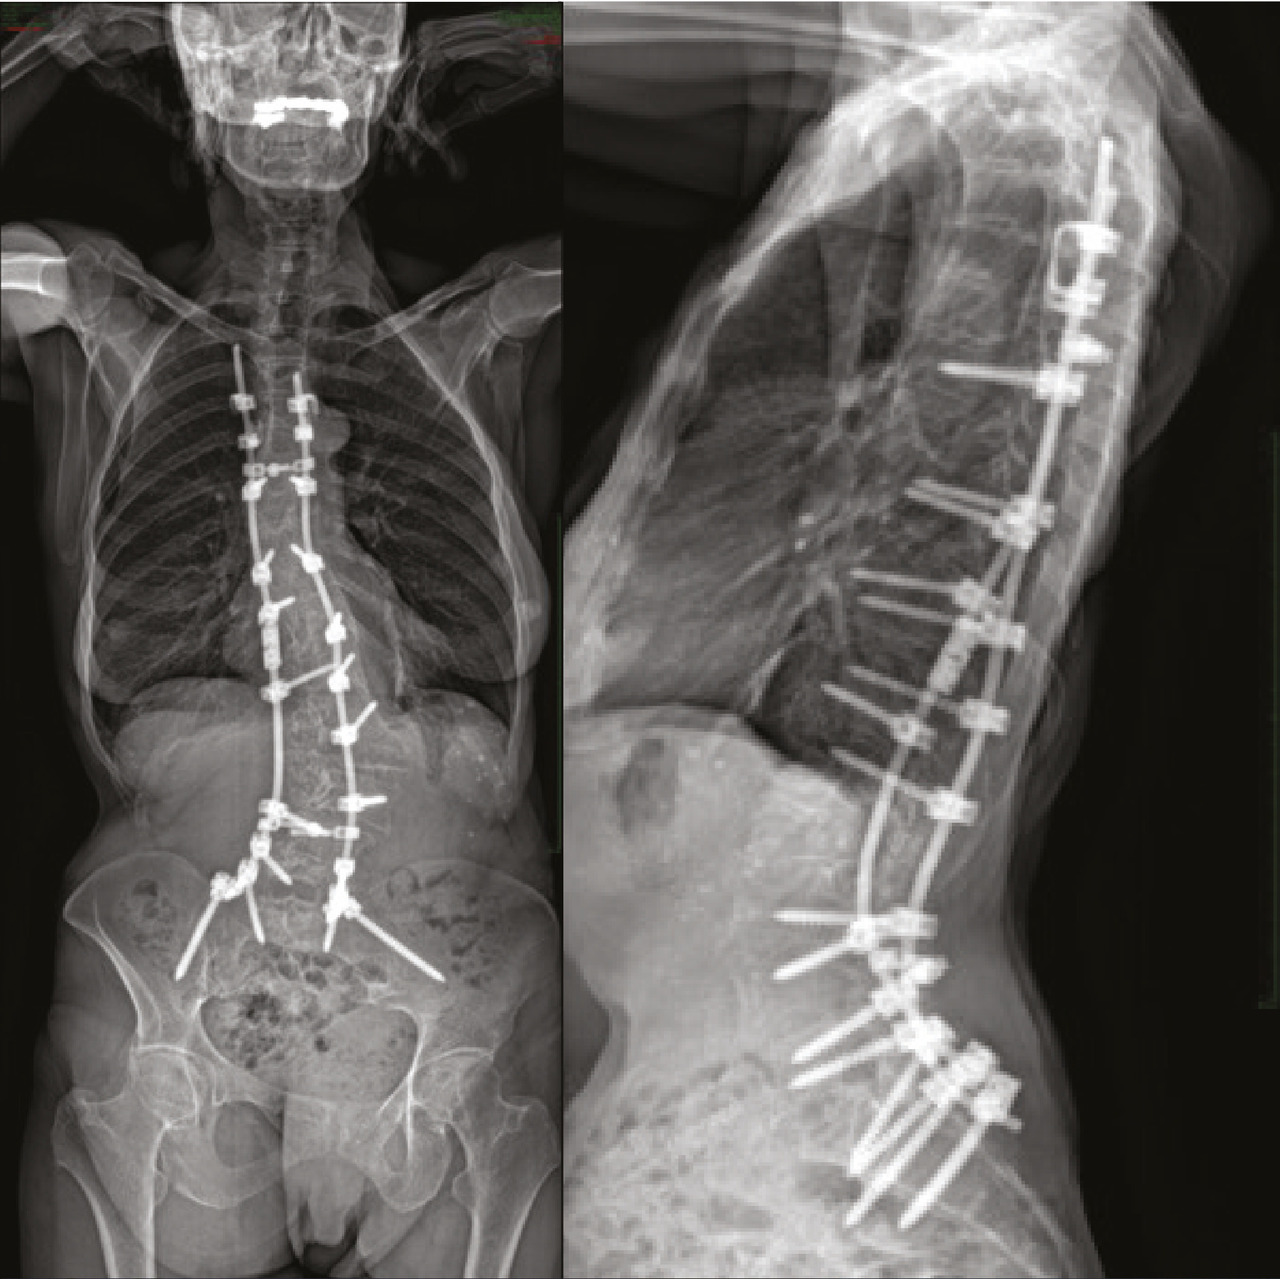

Système de Cotrel-Dubousset depuis les années 80 : plusieurs points d’ancrage permettent de se dispenser de toute contention postopératoire (fig. 2 ).

Une fois la greffe consolidée, plus de déformation (fig. 3 ) au fil des années, avec disparition des douleurs dans la zone opérée.

Chez l’adulte :

– les complications augmentent avec l’âge et les comorbidités ;

– en raison de la dégradation du rachis lombaire, les arthrodèses sont souvent plus longues, parfois jusqu’au sacrum : contraintes sur le matériel plus importantes, ancrage moins puissant dans un os moins solide ;

– pseudarthrose, fracture de tige et reprise chirurgicale : surtout après 40 ans.